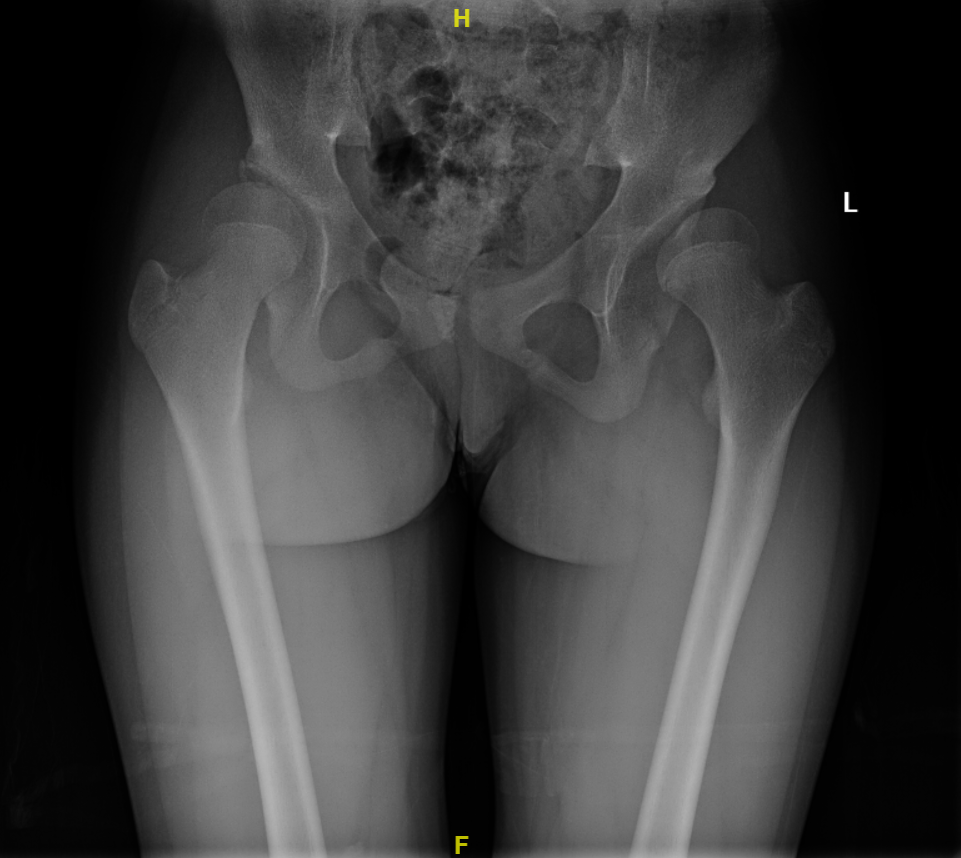

2021-01 双侧髋臼PAO截骨取钉术后:双髋关节正位X线片

2021-07 左侧髋臼PAO截骨取钉板术后:双髋关节正位X线片